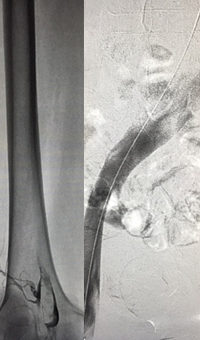

Xray of Iliofemoral thrombus pre-treatment and Power Pulse™ delivery

Iliofemoral thrombus pre-treatment (left) and Power Pulse delivery (right)

Xray of veins post-ZelanteDVT mechanical thrombectomy.

Post-ZelanteDVT  Mechanical Thrombectomy

Xray of veins post-ZelanteDVT runtime 415 seconds.

Post-ZelanteDVT runtime 415 seconds

Images Courtesy of Charles Wyble M.D. – Vascular Surgical Associates, Marietta, Georgia – January 5, 2016